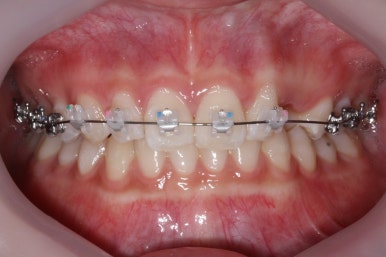

마무리 때의 사진입니다.

윗니만 부분교정하였지만 교합에도 이상 없이 매복되었던 송곳니는 매우 잘 위치를 잡았습니다.

송곳니 부위는 다시 틀어지지 않게 하기 위해 유지철사를 붙여주었습니다.

총 치료기간은 20개월 소요 되었습니다.

부산매복치아교정 상악 부분교정을 통해 매복치를 교정해준 이번 치료의 전후사진 비교입니다.

썩은 유치 대신 영구치 송곳니는 매우 자연스럽게 위치되었습니다. 아랫니는 교정하지 않았기 때문에 약간 삐뚠 느낌은 남아있지만 맞물림은 크게 문제가 없게 마무리 되었습니다.